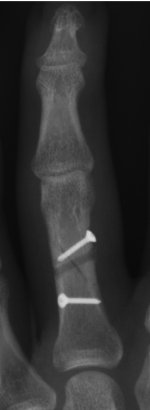

Ich hatte eine Mehrfachfraktur im Grundglied (Grundknochen). Hier sind 2 Schrauben drin diese sind vor dem Fingermittelgelenk. Das Fingermittelgelenk ist nicht betroffen. Schrauben sind weit vom Fingermittelgelenk entfernt wie ich es sehe. Siehe Anhang.

Anhänge

• Ringfinger.jpg

Ringfinger.jpg

36,1 KB · Aufrufe: 4